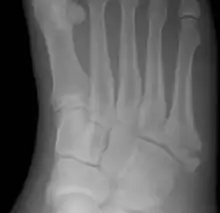

Diagnostic X-rays include anteroposterior, oblique, and lateral views and should be made with the foot in full flexion.

Pseudo-Jones fracture

Other proximal fifth metatarsal fractures exist, although they are not as problematic as a Jones fracture. If the fracture enters the intermetatarsal joint, it is a Jones fracture. If, however, it enters the tarsometatarsal joint, then it is likely an avulsion fracture caused by pull from the fibularis brevis tendon. An avulsion fracture at the base of the fifth metatarsal is sometimes called a "dancer's fracture" or a "pseudo Jones fracture", and usually responds readily to non-operative treatment.[18] The X-ray appearance of the developmental "apophysis" in this area may have some resemblance of a fracture, but is not a fracture; it is the secondary ossification center of the metatarsal bone. It is a normal finding that occurs at this site in adolescents.[19] If an injury to that area has occurred, the physician is often able to interpret certain radiographic clues to make the differentiation. An avulsion fracture at this location is typically extra-articular and oriented transversally as compared to the longitudinal orientation of an unfused apophysis.[19]